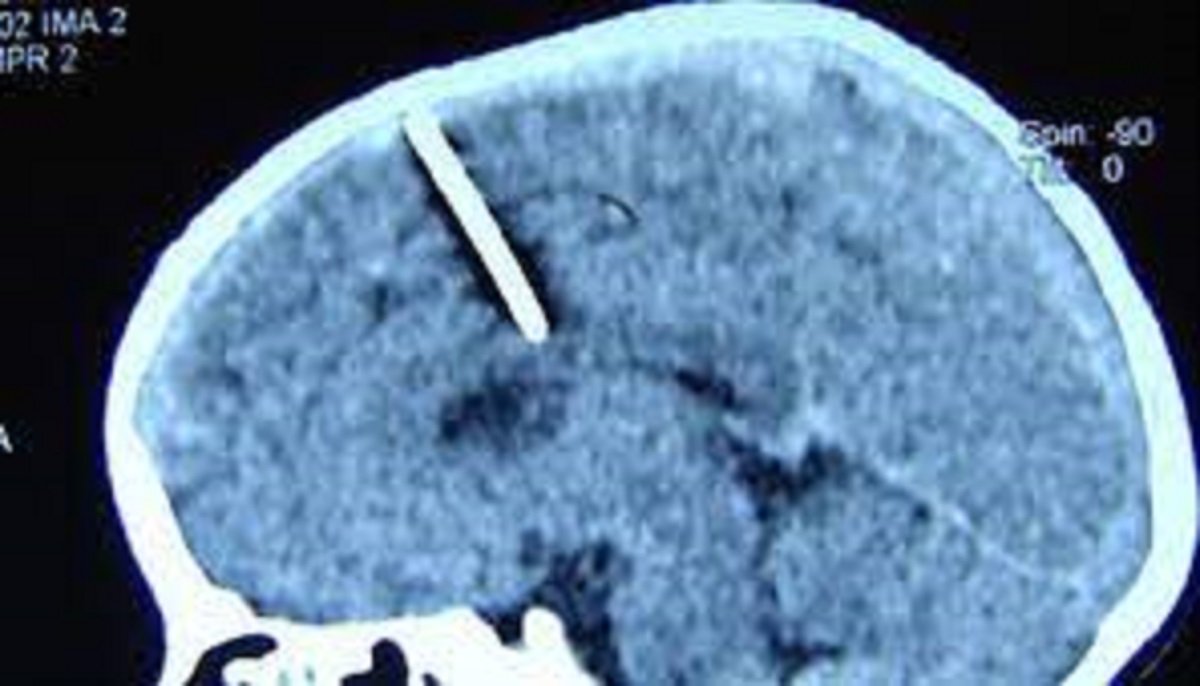

मस्को । रूसको सुदूर पूर्वकी एक वृद्धाले आफ्नो मस्तिष्कमा एक इन्च लामो सुईसहित ८० वर्षसम्म बाँचेको पत्ता लागेको छ । चिकित्सकहरूले ती महिलाको सीटी स्क्यान गर्ने क्रममा एक इन्च लामो सुईको टुक्रा भेटिएको जनाएका छन् ।

स्थानीय स्वास्थ्य विभागले भनेको छ, “सुई उनको बायाँ ‘पेरिएटल लोब’ (मस्तिष्क) मा छिरेको थियो, तर यसले अपेक्षित प्रभाव पारेन र बालिका बाँच्न सफल भइन् ।”